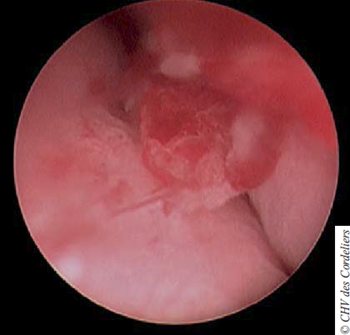

Un examen endoscopique urinaire est proposé pour évaluer le degré d’envahissement de la masse dans les zones difficilement accessibles par l’échographie et pour effectuer des prélèvements histologiques. La prémédication est assurée par de l’acépromazine (20 μg / kg IM) et du chlorhydrate de morphine (0,1 mg / kg IM). L’induction est réalisée au propofol à dose d’effet et le maintien à l’isoflurane à 2 % dans 1 litre d’oxygène. La chienne est placée en décubitus dorsal et une optique rigide de 2,7 mm est introduite dans les voies vaginales (photo 2).

Photo 2 : Vagino-cystoscopie par endoscopie rigide

Plusieurs nodules de 2 à 4 mm sont visualisés dans le vagin, obstruant le méat urinaire (photo 3).

Photo 3 : Nodule vaginal fermant le méat urinaire.

L’endoscopie se poursuit par le cathétérisme urétral ; aucune lésion visible n’est objectivée. L’examen de la vessie ne révèle pas de lésion en regard du trigone. En avant de celui-ci, la présence d’une masse hémorragique occupant la quasi-totalité de la lumière vésicale est confirmée.